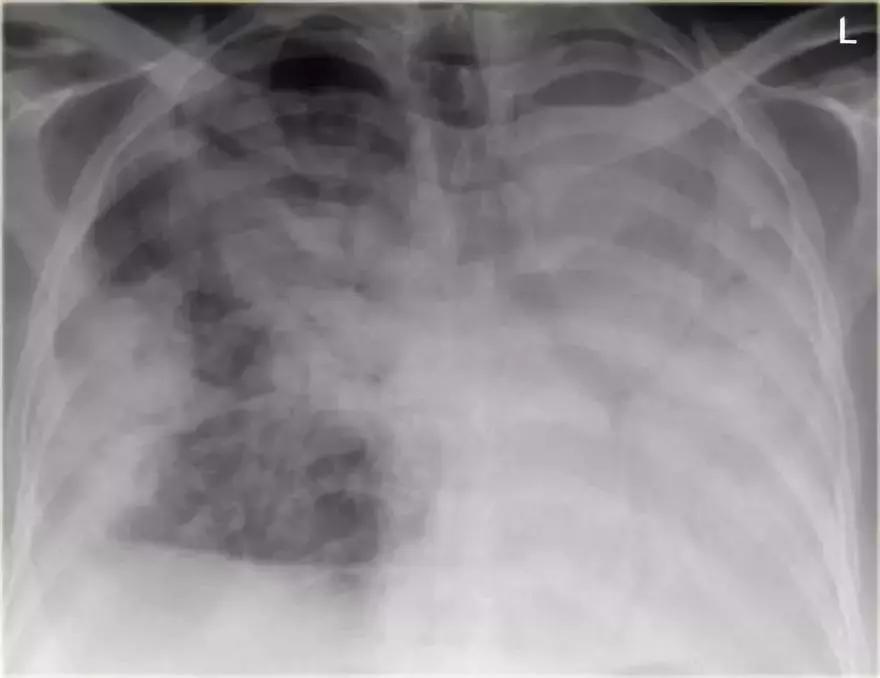

充血性心力衰竭

影像学信息:

➢ 双侧肺门实变,伴有空气-支气管征及边界模糊

➢ 心脏大小增加

➢ 间质轻微肺纹

➢ 血管蒂可能增大

图10 充血性心力衰竭

支气管肺炎弥漫性实变

➢ 患者患有高烧咳嗽,诊断为弥漫性支气管炎。

➢ 与始于肺泡的大叶性肺炎不同,支气管肺炎作为急性支气管炎始于气道。

➢ 多发模糊阴影,进展期能产生弥漫性实变,病变不能越过叶间裂,但通常在多个肺段发生。

➢ 支气管肺炎可由多种微生物引起

诊断结果:军团菌肺炎

图11 支气管肺炎弥漫性实变